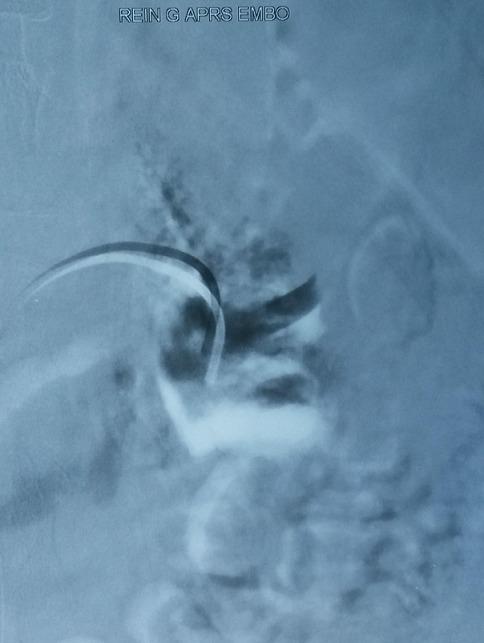

We report the treatment of a bleeding renal pseudoaneurysm by angio-embolization. A 21 years old woman developed macroscopic haematuria following renal biopsy. Renal angio-scan showed a 1.4 cm renal pseudoaneurysm in the left kidney. The presence of pseudoaneurysm was confirmed by selective renal angiography. Successful embolization was performed using gelatine sponge particles.

我们报告了一例通过血管栓塞治疗出血性肾假性动脉瘤的病例。一名21岁女性在肾活检后出现肉眼血尿。肾脏血管扫描显示左肾有一个1.4厘米的肾假性动脉瘤。通过选择性肾血管造影证实了假性动脉瘤的存在。使用明胶海绵颗粒成功进行了栓塞。